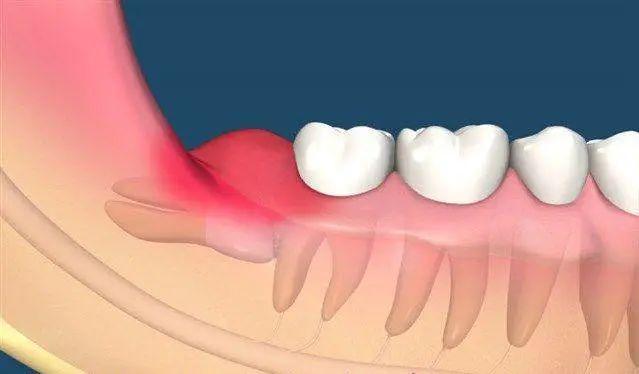

1,智齿阻生

智齿阻生就是指智齿因为生长空间不足等原因导致长不出来,或是长出不完全。这种情况往往会引起口腔局部的发炎疼痛,虽然短期内可以好转,但一旦生病或是身体有炎症又会复发;并且,对于长出不完全的智齿,也很容易导致食物塞嵌、不易清洁,引发其他口腔疾病。